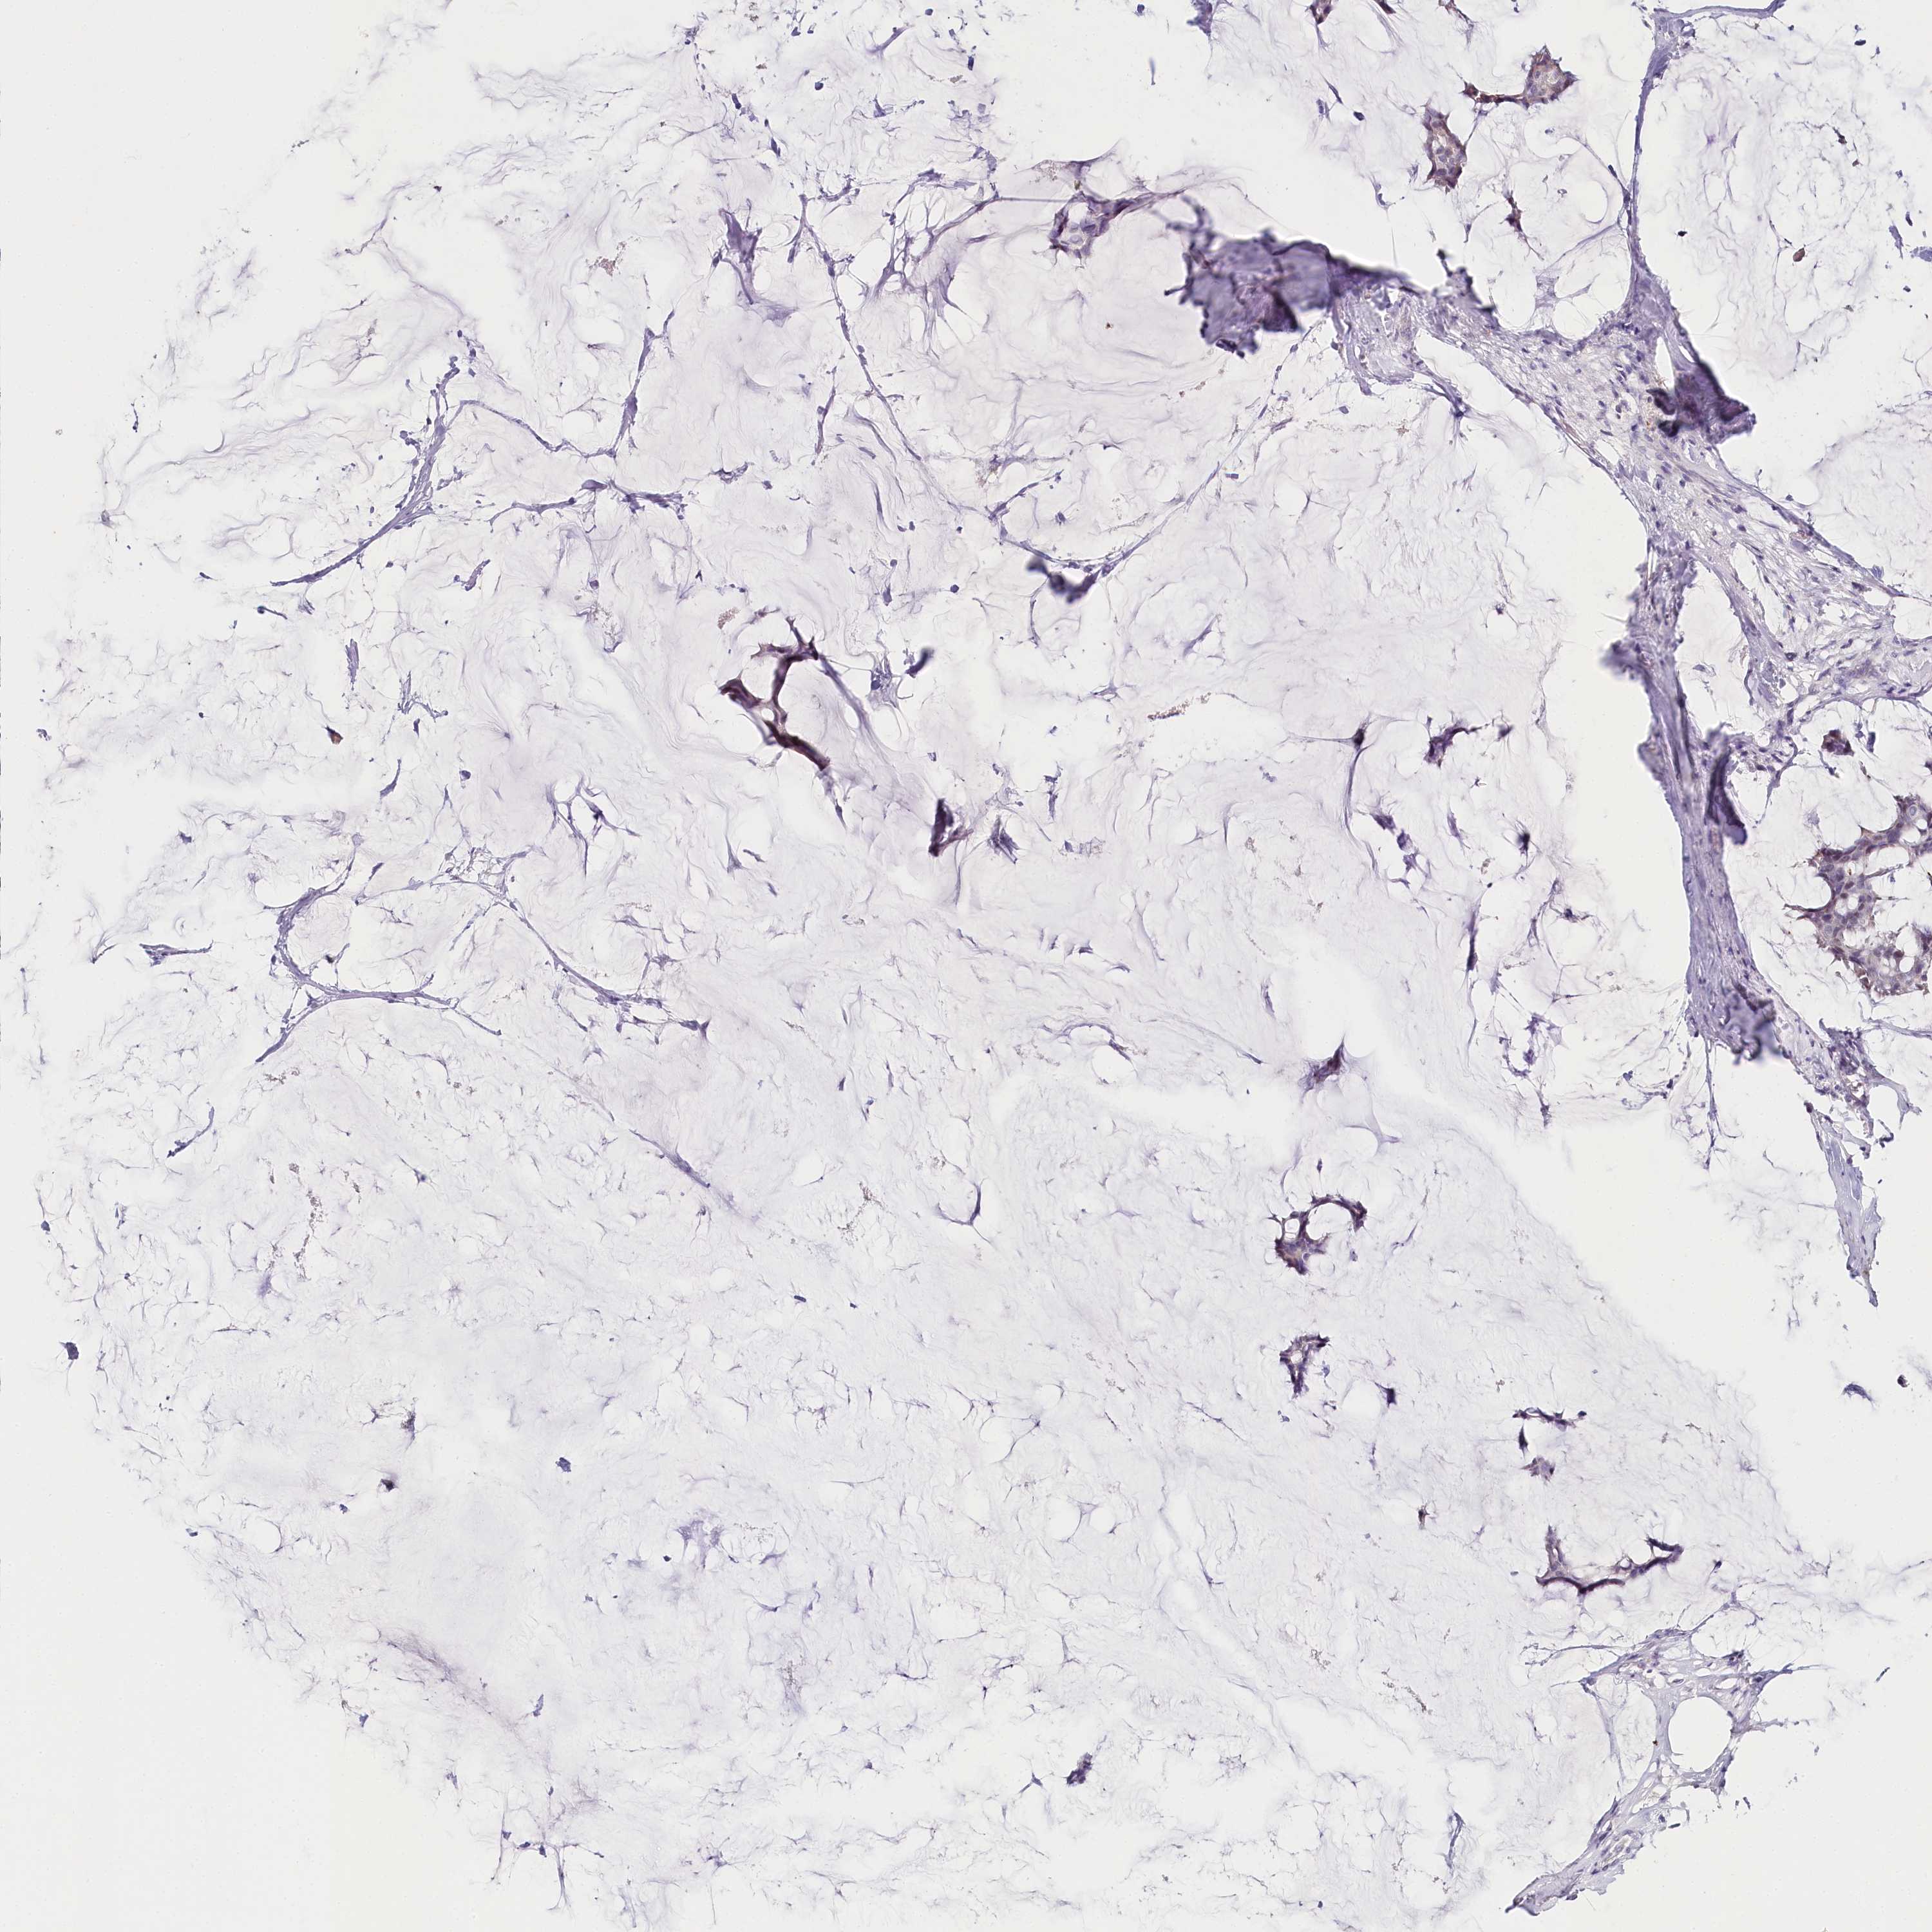

CANCER BREAST CANCER Show tissue menu

BRCA TCGA BRCA VALIDATION PROTEIN EXPRESSION